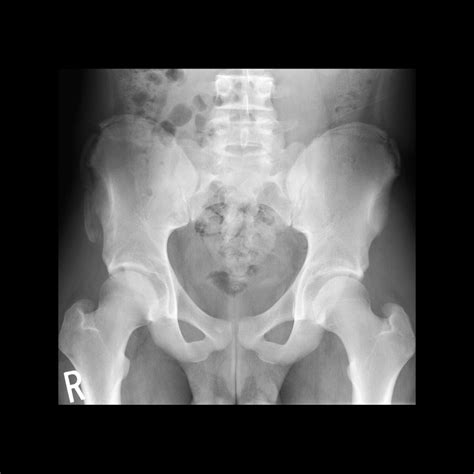

If you suspect an avulsion injury, professional medical diagnosis is vital. Doctors typically use physical examinations and imaging techniques to confirm the diagnosis. An X-ray is usually the first line of defense to visualize the bone fragment. In more complex scenarios, an MRI or CT scan might be ordered to evaluate the extent of soft tissue damage and the exact displacement of the bone.

Common sites for these fractures include:

• Ischial Tuberosity: Where the hamstring muscles attach (often during sprinting).

• Anterior Inferior Iliac Spine (AIIS): Where the rectus femoris (part of the quadriceps) attaches (often during kicking or jumping).

• Anterior Superior Iliac Spine (ASIS): Where the sartorius muscle attaches.

• Iliac Crest: Where the abdominal muscles attach.